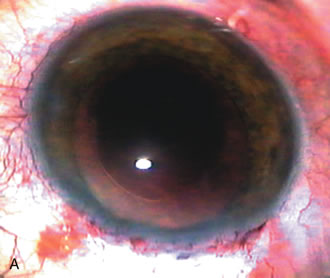

Fig. 1. The anatomic advantage of small incision cataract surgery for the glaucoma patient. A. Long-term bleb function with a large cataract incision is difficult to achieve with either ECCE-trabeculectomy or trabeculectomy followed later by ECCE. This bleb failed to form sufficiently when combined with large incision ECCE. The inflammation, bleeding, and long-term wound healing with stimulation of fibroblasts associated with this technique are more likely to cause bleb failure. In addition, the increased iris manipulation necessary to deliver the nucleus and subsequent iris repair adds to the long-term breakdown of the blood aqueous barrier. B and C. Two-site phacotrabeculectomy has the advantage of small incision cataract surgery combined with separate site trabeculectomy. The incision size is one third the size of the standard ECCE. The inflammation is less severe, and cataract wound healing is confined to the temporal area. Visual rehabilitation with phacoemulsification and foldable IOL is much faster. Phacoemulsification allows successful lens extraction even in the unfriendly environment of a smaller pupil compared with ECCE. The trabeculectomy is performed in an entirely different site, well away from the wound healing associated with temporal phacoemulsification. The likelihood of this filter functioning long-term is greater than with ECCE-trabeculectomy. D. The surgeon also has the option of single-site phacotrabeculectomy with foldable IOL. Both the lens extraction and trabeculectomy are performed through one small 3.5-mm limbal incision.

Fig. 3. Partial bleb failure following clear corneal phacoemulsification with foldable IOL. A. Preoperative bleb appearance prior to temporal lens extraction. Preoperative IOP was 12 mm Hg on no antiglaucoma medications. Time from 5-FU trabeculectomy surgery to lens extraction was one year. B. Bleb appearance 2 months after clear corneal cataract surgery with topical anesthesia. Following lens extraction, increased vascularity was noted along with decreased size of the filtering bleb. IOP increased to 20 mm Hg as early as 2 weeks after surgery, necessitating topical antiglaucoma therapy. C. High magnification view of bleb before lens extraction demonstrates diffuse pale bleb. D. High magnification view of bleb 2 months after surgery. There are vessels surrounding the nasal side of the bleb and the overall bleb size is smaller.